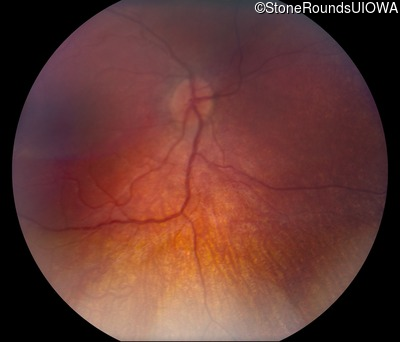

Fundus Photography - Right - No Light Perception

Exemplar